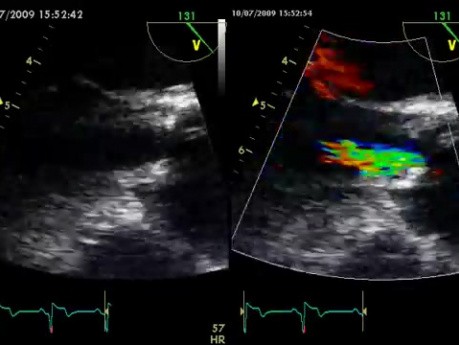

Niedomykalność Zastawki Aortalnej

Na filmie przedstawiono niedomykalność zastawki aortalnej. Obraz z ultrasonografu.